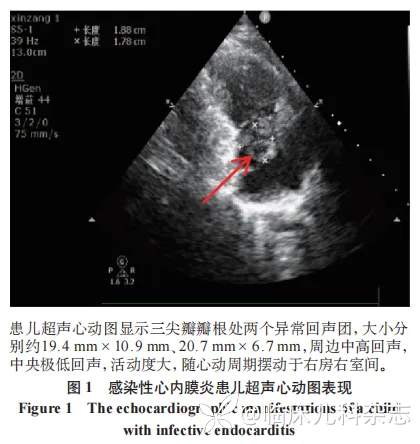

5 例患儿均为学龄期儿童,发病年龄 9(5.0~9.5)岁,其中男 3 例,女 2 例,所有患儿均有发热、咳嗽表现,1 例伴有剑突下疼痛,1 例伴有胸痛、咯血、呼吸困难,1 例伴有低氧及低血压表现,发热持续时间 12(9.5~15)天。所有患儿 D 二聚体 5.09 (4.35~7.90 )μg/mL 及 FDP 10.56(7.20~24.71) mg/L 明显增高,IL-6 55.45 (33.02~95.56) pg/mL、LDH746 (568.45~838.90)U/L 亦有增高(表 1)。所有患儿均符合重症 MPP 表现,完善彩色多普勒超声心动图评估心脏结构及功能,5 例患儿超声心动图均提示右心室或右心房腔内等高回声,部分伴有中央低回声或不均匀回声(图 1),发现赘生物的时间为病程第 10(8~12)天。胸片或 CT 检查均提示存在肺部实变,其中 3 例患儿因 D 二聚体> 5 mg/L 进行肺部增强 CT 检查可见肺动脉栓塞(2 例右侧,1 例左下),见图 2。所有患儿进行咽拭子或痰液肺炎支原体核酸检测结果阳性,耐药基因位点检测均为阳性,血清 MP 抗体滴度检测均 ≥ 1∶320,痰培养及血培养阴性,赘生物标本蜡块外送病原学宏基因检测均阴性,1 例送检血流 NGS 检出 MP 阳性。